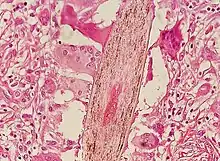

Folliculitis is infection or inflammation of one or more hair follicles resulting in one or more small pustules or red bumps.[1] These are generally tender and may be itchy.[2] The condition may occur anywhere on hair covered skin.[1][3] Complications include cellulitis or abscess.[1]

Folliculitis starts with the introduction of a skin pathogen to a hair follicle. Hair follicles can also be damaged by friction from clothing, an insect bite,[5] blockage of the follicle, shaving, or braids that are too tight and too close to the scalp. The damaged follicles are then infected by Staphylococcus. Folliculitis can affect people of all ages.